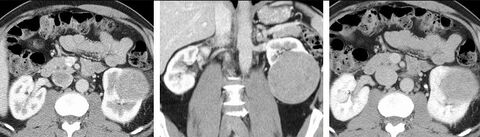

Detection and characterization of renal parenchymal masses is a frequent indication for CT. An initial noncontrast CT is important for detecting calcium or fat in a lesion, and to provide baseline attenuation of any renal masses. Following noncontrast scanning, intravenous contrast is injected and a corticomedullary phase is obtained at approximately 70 seconds (figure 7a, 7b). The corticomedullary phase is characterized by enhancement of the renal cortex as well as the renal vasculature. This phase is valuable in the evaluation of benign renal variants, lymphadenopathy and vasculature, however certain medullary renal masses may not be visible during this phase due to minimal enhancement of the medulla and collecting system. The parenchymal phase is obtained approximately 100–200 seconds after the injection of contrast material (figure 7c). Parenchymal phase imaging demonstrates continued enhancement of the cortex, enhancement of the medulla, and various levels of contrast material in the collecting system. The parenchymal phase is highly important for the detection and characterization of renal masses, parenchymal abnormalities, and the renal collecting system. This method of imaging does not evaluate for abnormalities of the collecting system.[citation needed]

Common renal masses can occasionally be differentiated from each other using this imaging technique. Renal cell carcinomas and oncocytomas typically demonstrate intense heterogeneous enhancement on the parenchymal phase images and cannot be reliably differentiated from each other but can be distinguished from other renal masses. Angiomyolipomas (AML’s) also demonstrate intense contrast enhancement but characteristically contain macroscopic fat which can be detected on the noncontrast images, and can help to differentiate AML’s from renal cell carcinomas and oncocytomas. Renal lymphoma on the other hand, will often have decreased enhancement when compared to the renal parenchyma on the parenchymal phase images.[citation needed]

FIGURE 7. Selected images from a renal mass specific protocol CT. Corticomedullary phase (axial 7a) demonstrates peripheral enhancement of the renal cortex with minimal opacification of the renal medulla. There is a large renal cell carcinoma in the left kidney (right in image) which can be differentiated from the normal renal parenchyma by the heterogeneous and differential enhancement. The renal artery and vein are opacified in this phase as well. The collecting system is not opacified (coronal reformat 7b). In the parenchymal phase, the renal cortex and the medulla are enhancing. The renal cell carcinoma in the left kidney is not as well defined when compared to the corticomedullary phase images, but is actually slightly more conspicuous. There is some contrast noted within the collecting system during this phase (7c).[citation needed]